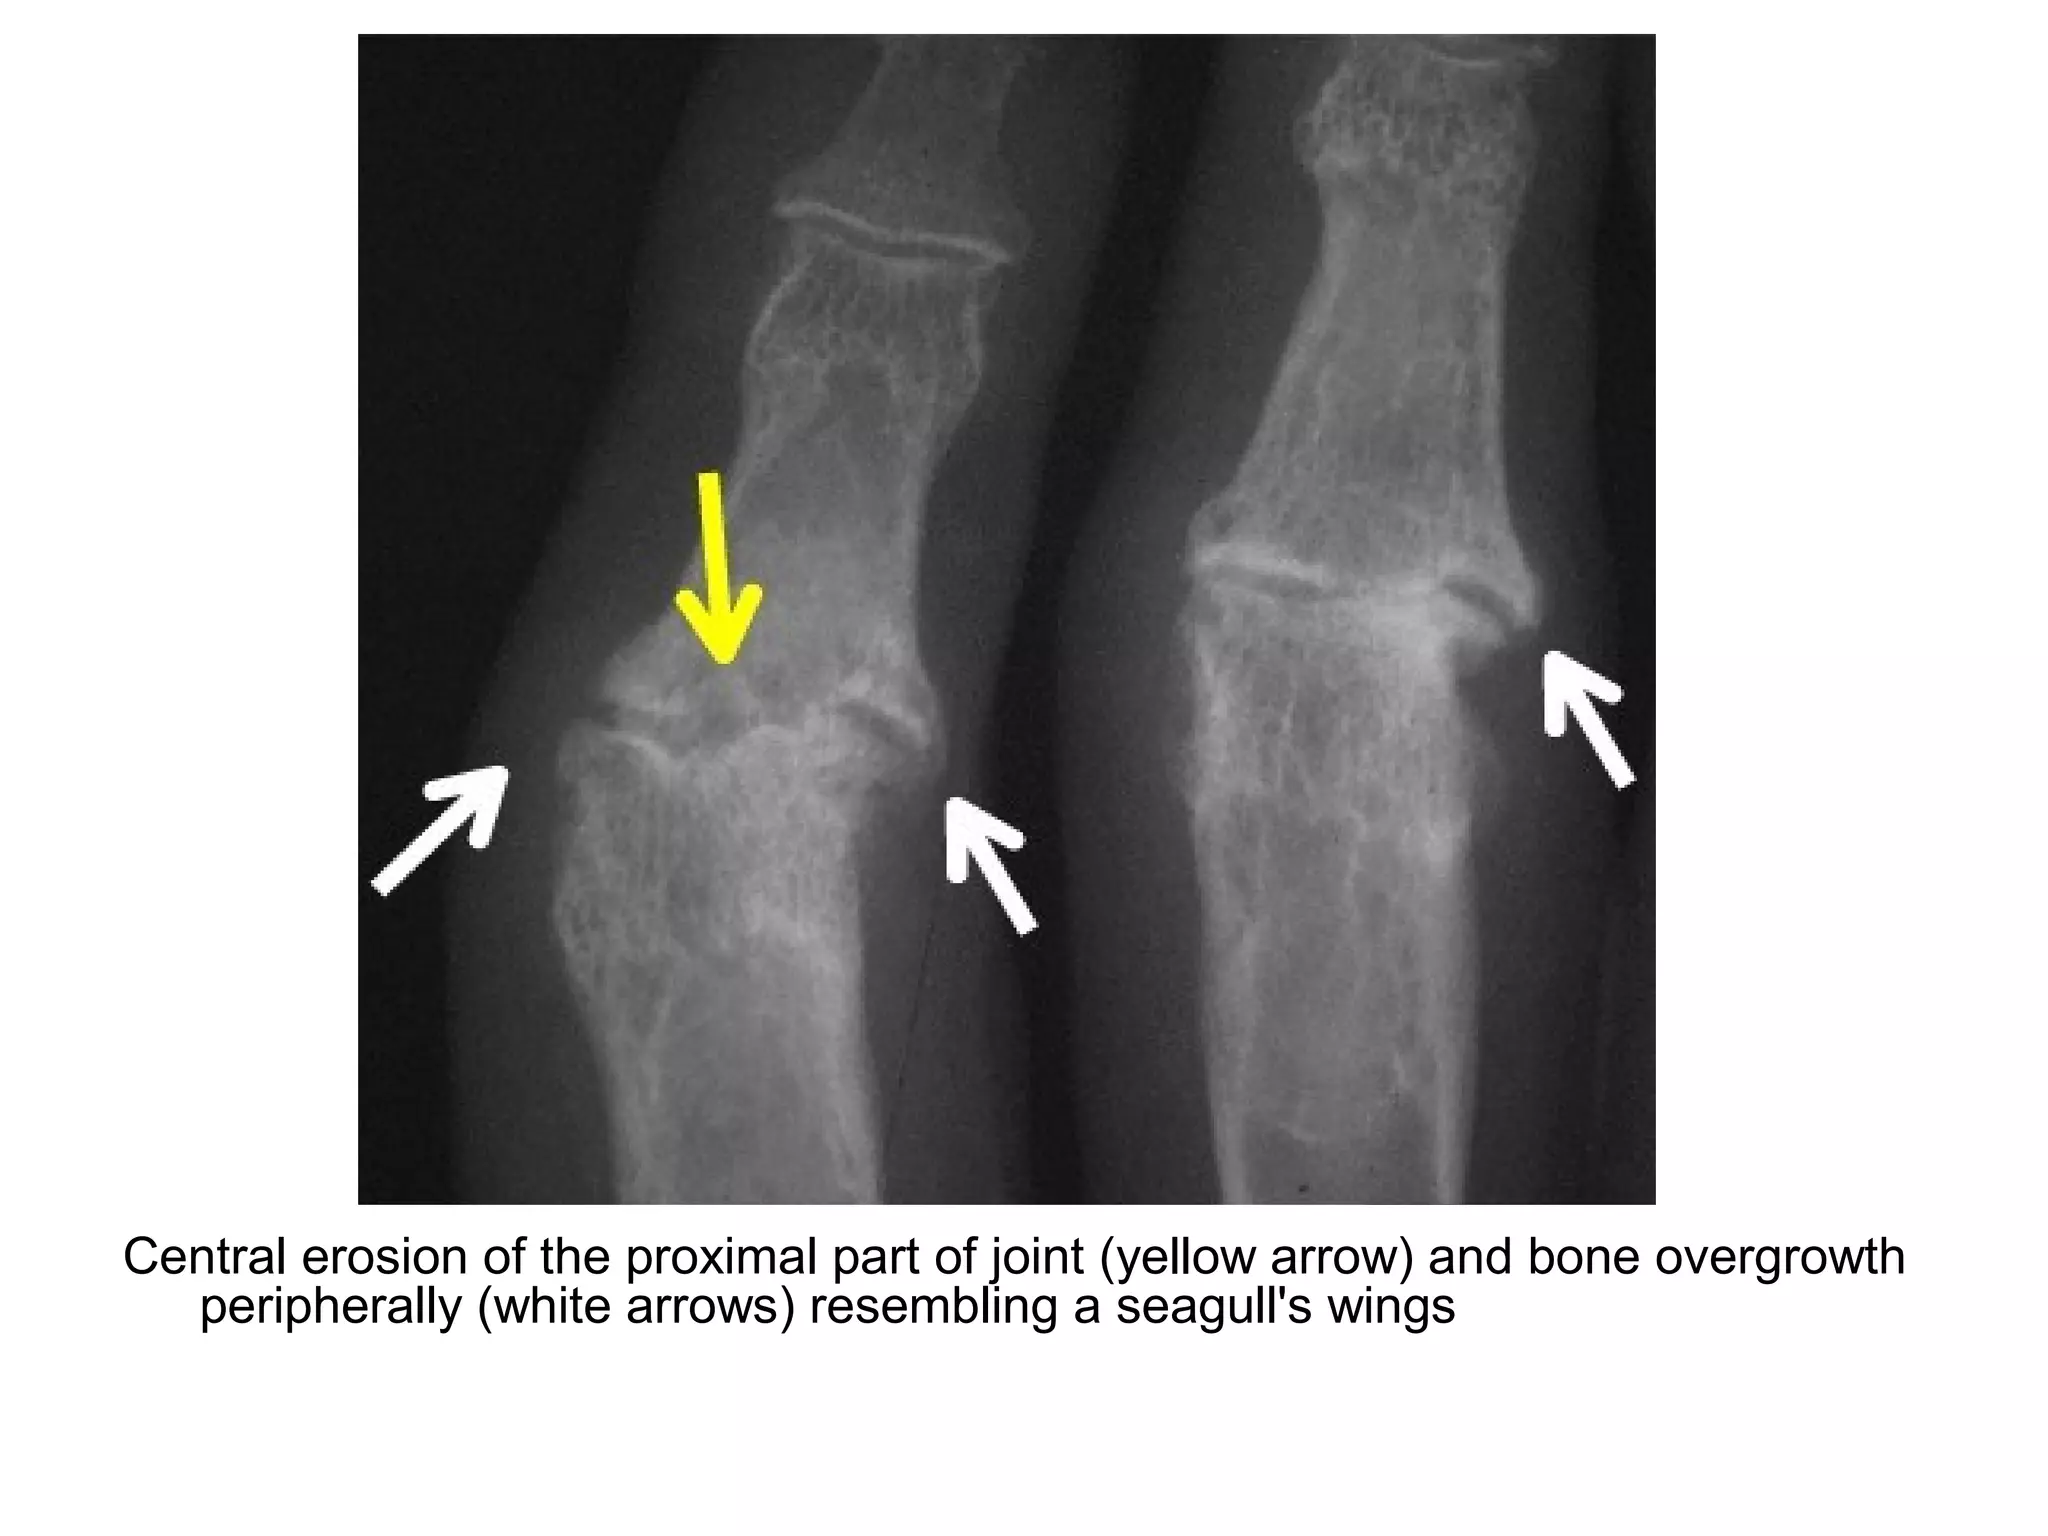

-Sea-Gull wing appearance (the combination of cartilage

space loss , subchondral central erosions & osteophyte

formation)

Gull wing appearance

Gull wing appearance of the DIP (arrows)

Gull wing deformities in erosive arthritis , cartilage loss and bone remodeling at the

middle and ring finger proximal interphalangeal joints produce a gull wing appearance

Central erosion of the proximal part of joint (yellow arrow) and bone overgrowth

peripherally (white arrows) resembling a seagull's wings